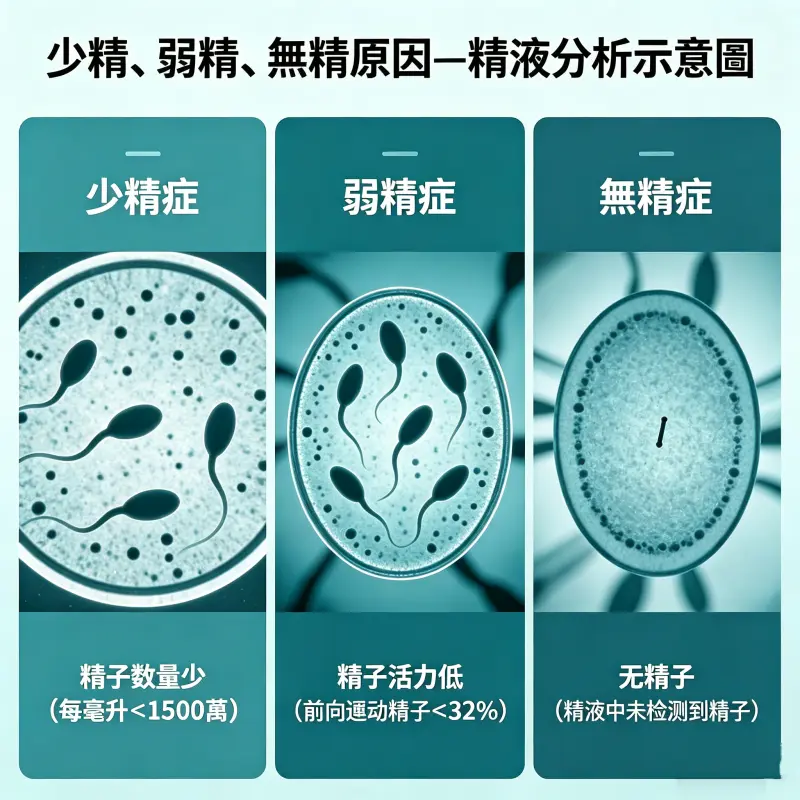

一、什麼是少精、弱精、無精?

在探討「少精、弱精、無精原因」之前,需先了解基本定義:

少精癥(Oligospermia):精子濃度低於1500萬/ml

弱精癥(Asthenozoospermia):精子活動力低於40%

無精癥(Azoospermia):精液中完全沒有精子

這三種情況是影響男性生育能力的主要因素。

少精、弱精、無精